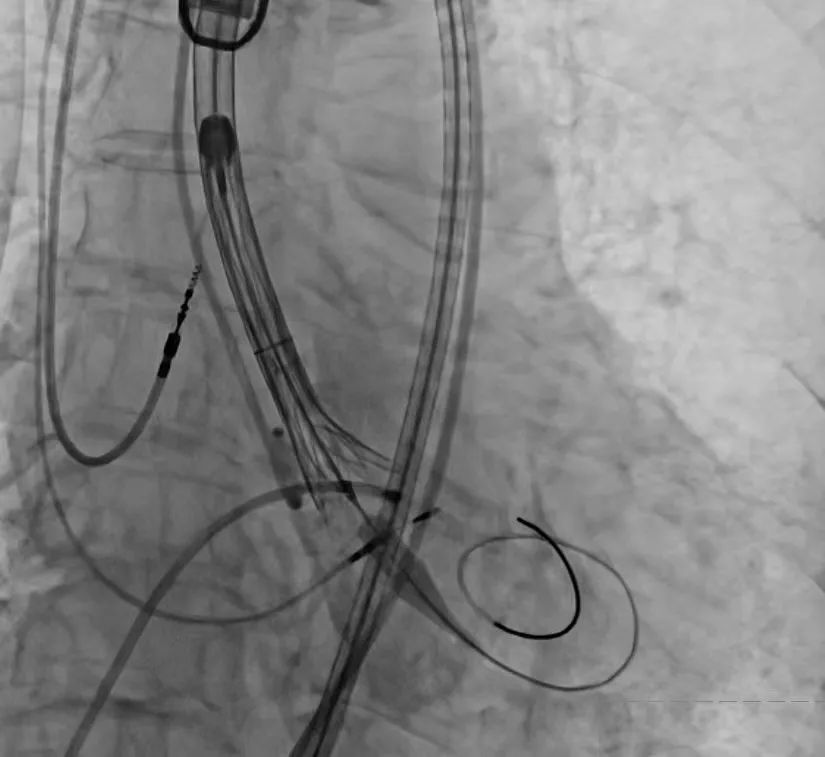

手术过程严谨有序:经术前精准评估与周密准备,团队成功送入预先装载的自膨式支架瓣膜输送系统,顺利完成过弓、跨瓣操作;经造影定位后,在180bpm快速起搏下精准释放瓣膜。瓣膜释放后,术中实时超声显示根部瓣架形态良好、启闭正常,瓣叶中心及瓣周未见反流;造影显示瓣膜位置满意、形态良好,冠脉显影清晰,入路血管无损伤,历经90分钟后,手术圆满成功。

术中影像